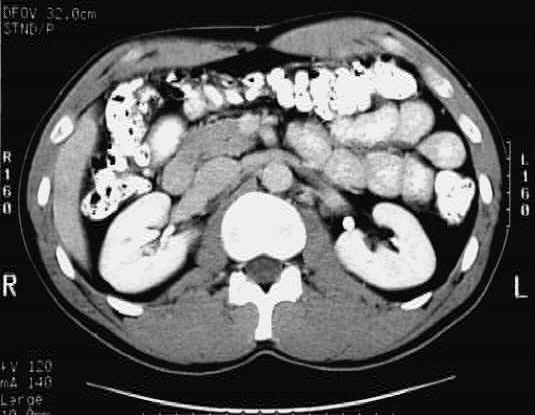

Abdomen_Cross_4 :